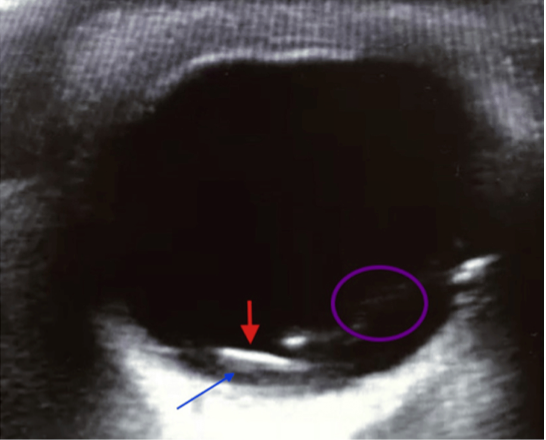

眼球内異物

Feldman M, Shigyo K, Kaji A: Intraocular foreign body: ultrasound and CT findings . J Educ Teach Emerg Med. 2017, 28-30. より引用

- 上図の赤矢印は金属片

- 高エコー構造として描出され硝子体出血を示唆する線状エコーを伴う場合がある